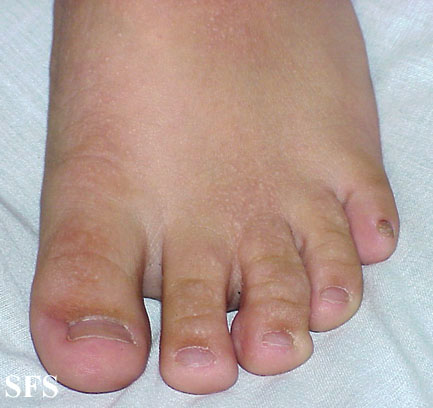

buschke-ollendorf syndrome